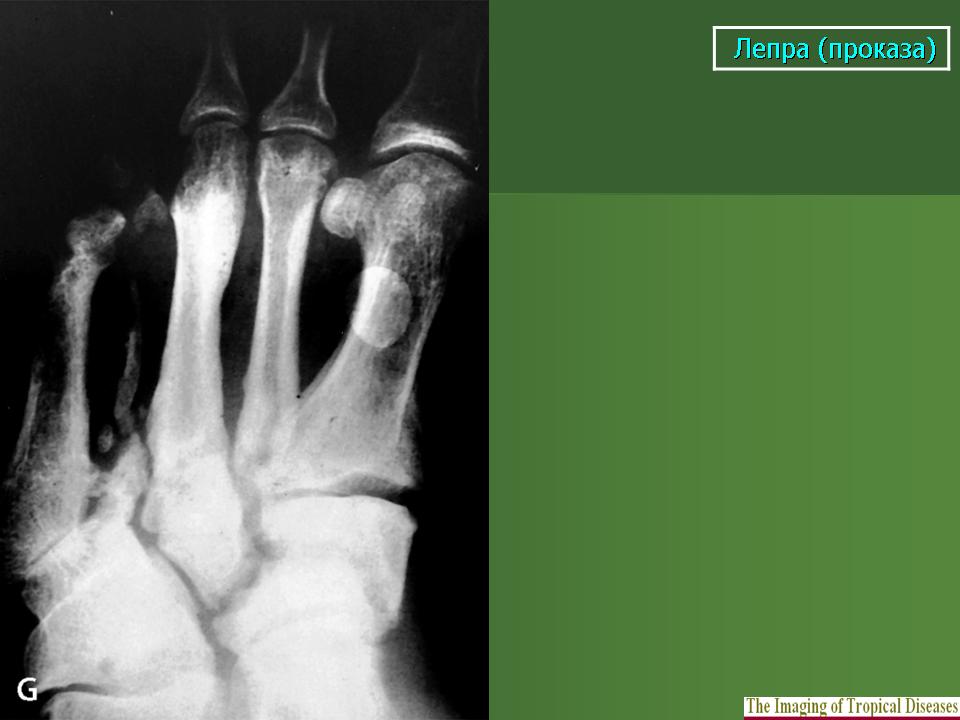

В третьей группе костных изменений при проказе (рис. 217, 218) сочетаются элементы первых двух групп, т. е. специфические и неспецифические. Из особенностей проказы вытекает крайняя неповторяемость частных проявлений в каждом индивидуальном случае заболевания.